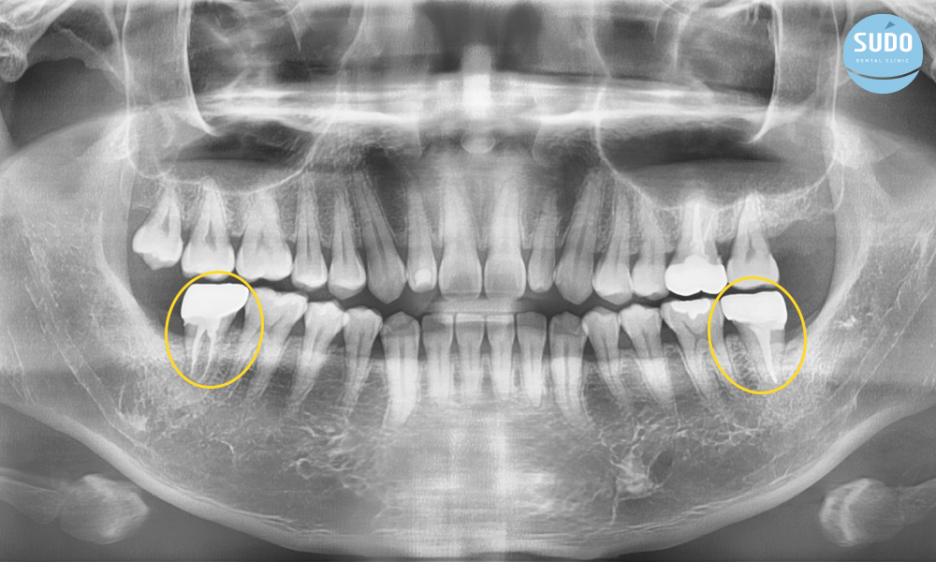

양쪽 사랑니를 뽑은 후 앞어금니들은 신경치료를 하고 크라운을 씌운 상태입니다.